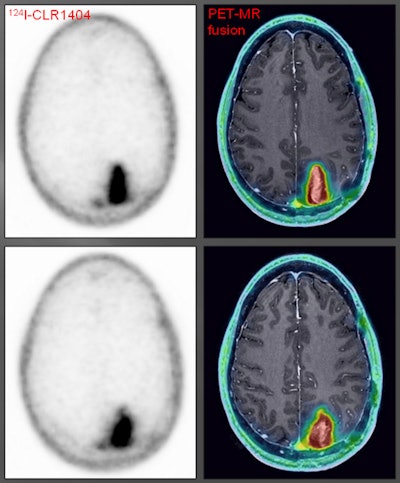

Winner: PET of patient with grade III glioma using iodine-124 (I-124) CLR1404 radiopharmaceutical

This year's Best Radiology Image award went to researchers from the University of Wisconsin for their image series demonstrating a new PET radiopharmaceutical for brain imaging. They believe the agent could more effective than nuclear medicine's workhorse tracer, FDG.

The team led by Dr. Lance Hall, an assistant professor of radiology at the university's UW Health system, has been investigating iodine-124 (I-124) CLR1404, which is being developed for both diagnostic and therapeutic applications.

CLR1404 is designed to enter cells through membrane lipid rafts, which are overexpressed in cancer cells and serve as a platform for cell proliferation. The agent is taken up by cancer stem cells, which are difficult to eradicate and can lead to disease recurrence and progression if they are not eliminated.

Studies in preclinical models have demonstrated that CLR1404 is more cancer-specific and targets cancers rather than inflammation or false positives that might be found on FDG-PET scans. In the study that resulted in the award-winning images, 16 patients with primary or metastatic brain tumors were injected with the radiopharmaceutical.

CLR1404 successfully imaged tumors with high tumor-to-background uptake and uncovered larger tumor volumes than contrast-enhanced MRI, the researchers found. There was no significant uptake of CLR1404 in normal areas of the brain and no uptake in regions that were treated for cancer and were presumably tumor-free.